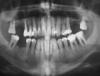

persifal Опубликовано 10 июня, 2010 Поделиться Опубликовано 10 июня, 2010 Добрый день,Посмотрите, пожалуйста, мой панорамный снимок. Очень рассчитываю на ваш профессионализм в оценке текущего состояния и, конечно, главный вопрос: что делать?44 года, подвижность зубов (особенно нижних резцов), пародонтит/пародонтоз, кюретаж делал 4 года назад, ситуация только ухудшается.Снимок также здесь - http://s61.radikal.ru/i173/1006/3c/aed6969bdcc8.jpg Заранее благодарю всех ответивших.Антон Ссылка на комментарий

Bier Опубликовано 10 июня, 2010 Поделиться Опубликовано 10 июня, 2010 тотальное удаление, имплантация. Ссылка на комментарий

Bier Опубликовано 10 июня, 2010 Поделиться Опубликовано 10 июня, 2010 внизу должно хватить, наверху синуслифтинг надо будет делать, если повезет, то в один этап с имплантацией, если нет, то в два. времени займет около 8ми месяцев, если не делать тотальную реконструкцию костной ткани, а ставить имплантаты в имеющуюся кость. Ссылка на комментарий